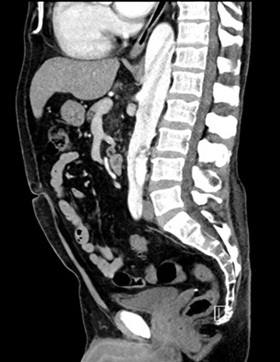

The gold standard for diagnosis is the computed tomography angiography (CTA) because of its speed, high sensitivity, and high specificity for aortic pathology. The sensitivity and specificity of CTA for acute aortic dissection approaches 100%.1,4,28-30 (See Figures 2-4.) An important point when ordering the CTA is to specifically state the reason, such as “possible aortic dissection,” so the correct CT imaging protocol will be done to maximize accuracy.

Figure 4. CTA Showing Aortic Dissection in Abdominal Aorta with Sagittal View |

![]() |

Image courtesy of Daniel Migliaccio, MD |